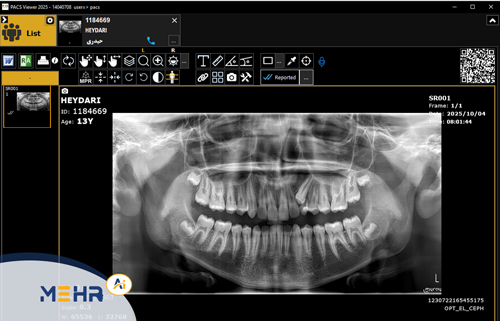

پکس MRI مهر، سامانه‌ای مبتنی بر استاندارد جهانی DICOM 3.0 است که وظیفه دریافت، ذخیره، پردازش و نمایش تصاویر MRI را بر عهده دارد.

این سیستم داده‌های تصویری حاصل از دستگاه‌های MRI را به‌صورت خودکار به سرور منتقل کرده و از طریق نرم‌افزارهای PACS Viewer MedScope یا Web DICOM امکان مشاهده و تحلیل آن‌ها را فراهم می‌کند.

پکس MRI با قابلیت اتصال مستقیم به نرم‌افزار پذیرش MedFlow و سایر سیستم‌های پکس، گردش‌کار مراکز تصویربرداری را به‌شکل کاملاً متمرکز و منظم سامان‌دهی می‌کند.

• مشاهده تصاویر MRI در نماهای Axial، Sagittal، Coronal

• ابزارهای پیشرفته برای Zoom، Rotate، Window Level و Distance Measurement

• مقایسه تصاویر چندمرحله‌ای بیماران برای بررسی روند درمان

• بازسازی سه‌بعدی (3D Reconstruction) از داده‌های حجمی MRI

• قابلیت Tagging و Annotation برای تهیه گزارش‌های دقیق